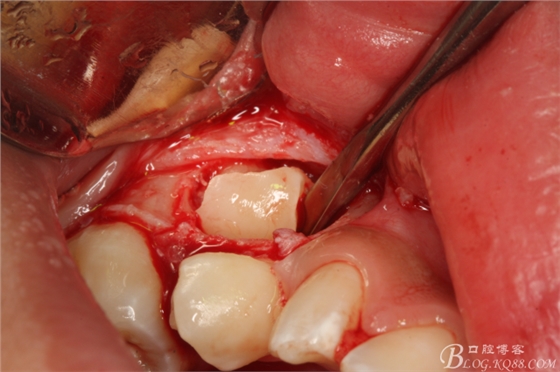

圖8.取出牙冠

圖8. 摘除牙囊